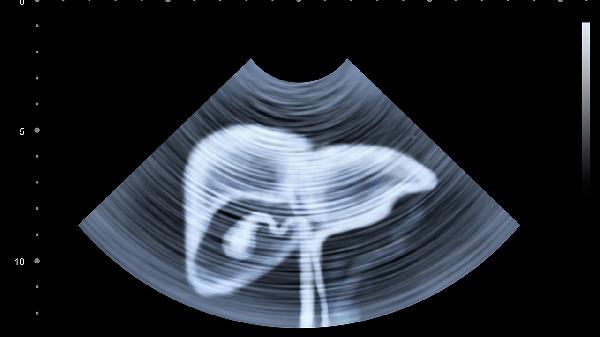

1、每年做一次肝功能检查,40岁以上建议加做肝脏超声